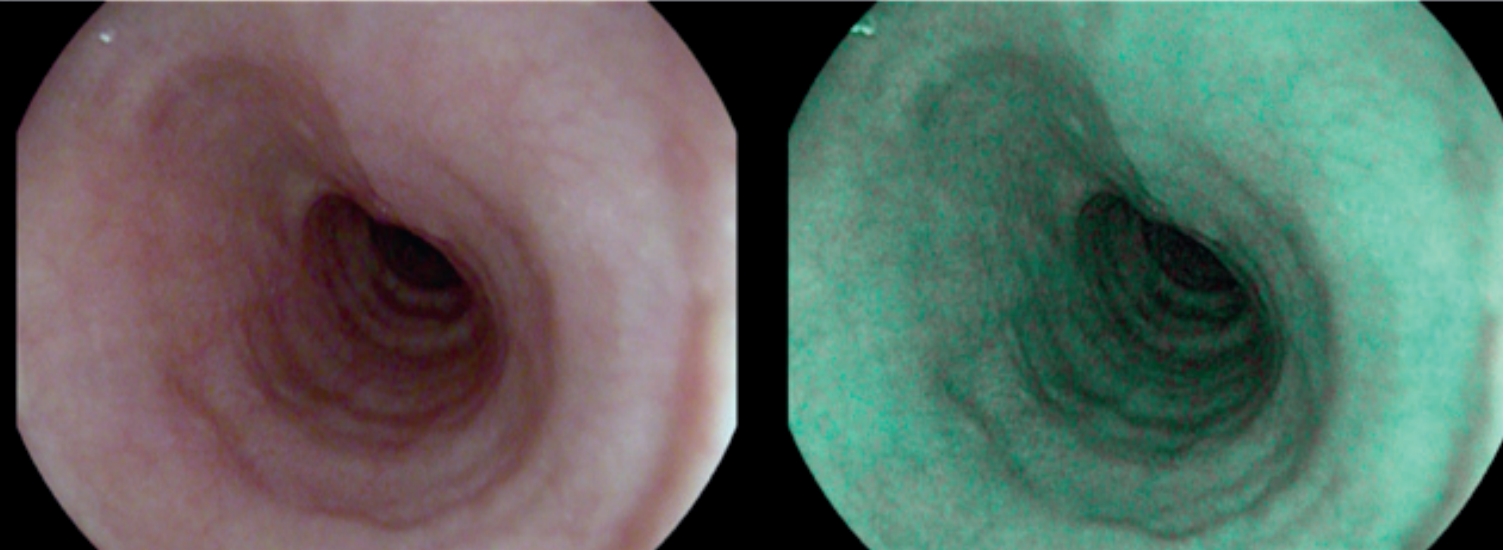

Рис. 1F. Шаг 6. Макроскопическая оценка отдаленных результатов эндоскопического хирургического лечения.

Fig. 1F. Macroscopic evaluation of long-term results of endoscopic surgical treatment.

Более детальная оценка в зоне проведения полипэктомии подтверждает отсутствие рецидива.